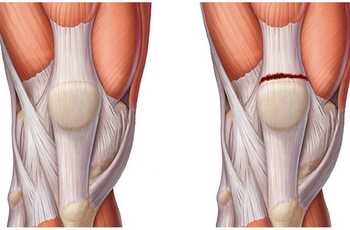

Нога человека сгибается в колене благодаря наличию мышцы-разгибателя, расположенной на передней части бедра. Она называется четырехглавой мышцей – состоит из четырех пучков мышечных волокон, каждый из которых имеет свое название. Все составляющие квадрицепс-мышцы имеют общее сухожилие, прикрепленное к надколеннику. Оно достаточно эластично и обладает высокой прочностью. А вот места перехода мышцы в сухожилие и крепления сухожилия к кости являются точками уязвимости квадрицепса при различных травматических воздействиях.

Чаще всего сухожилия четырехглавой мышцы бедра подвержены растяжению, частичному или полному разрыву, а также тендиниту – воспалительному процессу ткани сухожилия.

• Частичный или полный разрыв дистальных сухожильно-мышечных единиц группы четырехглавой мышцы бедра

• Сухожилие четырехглавой мышцы = общий дистальная сухожильная единица прямой мышцы бедра, медиальной, промежуточной и латеральной широкой мышц, прикрепляющихся к надколеннику